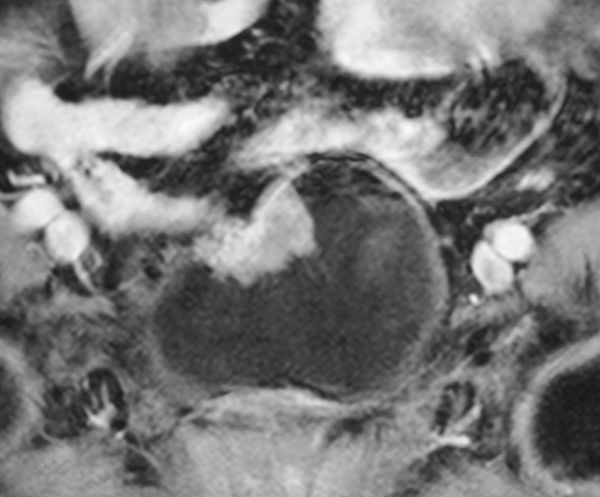

Рецидив колоретального рака в стенке мочевогопузыря